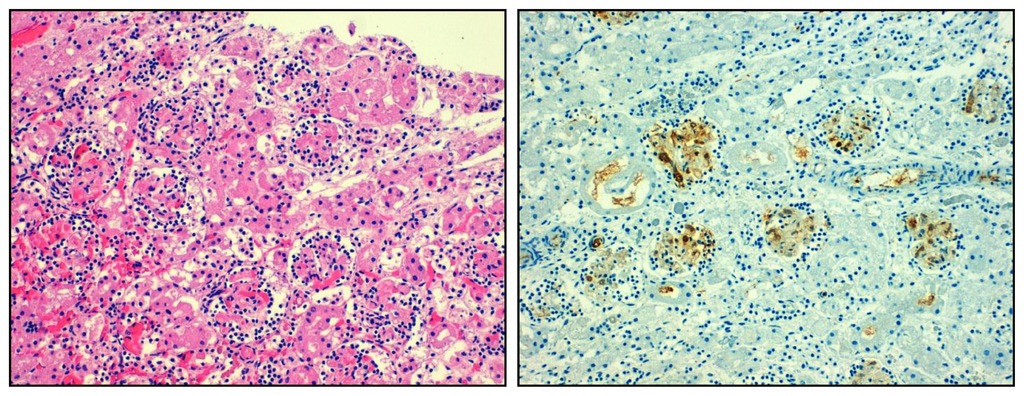

- Smeets, B.; Angelotti, M.L.; Rizzo, P.; Dijkman, H.; Lazzeri, E.; Mooren, F.; Ballerini, L.; Parente, E.; Sagrinati, C.; Mazzinghi, B.; et al. Renal progenitor cells contribute to hyperplastic lesions of podocytopathies and crescentic glomerulonephritis. J. Am. Soc. Nephrol 2009, 20, 2593–2603. [Google Scholar]